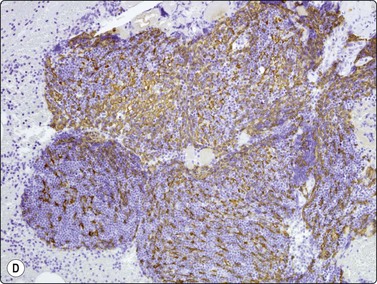

Fig. 9.1 Thymoma, lymphoepithelial

(A) Cohesive fragments of tumor tissue in a background of lymphoid cells (Pap, LP); (B) Cohesive cluster. Epithelial cells visible centrally Pap HP; (C) Cell block, indistinct epithelial cells (H&E, HP); (D) Cell block, reticular pattern of epithelial cell staining for AE1+3 keratins (IPOX, LP).

The histologic classification of thymomas is complex, evolving, and still somewhat controversial. Such subclassification may prove challenging for the histopathologist and this is exaggerated with aspiration cytology. Clearly, there is a wide spectrum in the cytomorphology of thymomas. First, there is a broad range of appearances of benign thymoma cells among and even within some of these neoplasms; this is complicated by the varying proportions of lymphocyes present.

In the benign thymomas, the epithelial cells are usually cohesive (Figs 9.1, 9.5) but may also manifest a reduction in intercellular cohesion (Fig. 9.2). Epithelial cells are not immediately evident in the mixed tumors at low power but are discernible using the higher magnification.18,29,30 The epithelial cells are polygonal, oval, or spindle shaped with uniform to slightly irregular nuclear outlines possibly with cleaved or folded nuclei. Their nuclear chromatin is homogeneous, finely distributed and pale and, occasionally, small nucleoli are seen. Cell borders are indistinct, but nuclei are separated by moderate amounts of pale cytoplasm (Figs 9.2, 9.5). In one personally examined case of thymoma metastatic to lung, Hassall’s corpuscles were evident in the clumps of tumor cells (Fig. 9.4); this is a most unusual manifestation and will not be present in most thymomas. When there is a lymphoid population, the bimodal pattern enables one to make a virtually certain diagnosis.18,29,30 In pure epithelial or spindle cell forms, definitive diagnosis is more difficult, although in Dahlgren’s series29 most thymomas were diagnosed and in Tao’s 37 cases30 all FNAC diagnoses of thymoma were verified histologically. Ali and Erozan34 were able to diagnose all of their 14 cases using a combination of cytology, immunocytochemistry and clinical information, and Shin and Katz showed a high accuracy in a range of mediastinal lesions including 14 thymomas.35 Tao and others describe more variation in the degree of cohesion than we have seen, particularly in pure epithelial/nonspindle cell types.30 Overall, the most challenging and the most common in our experience are the lymphocyte-rich (type B1) thymomas, as the tumor cells may be obscured by the lymphocytes.